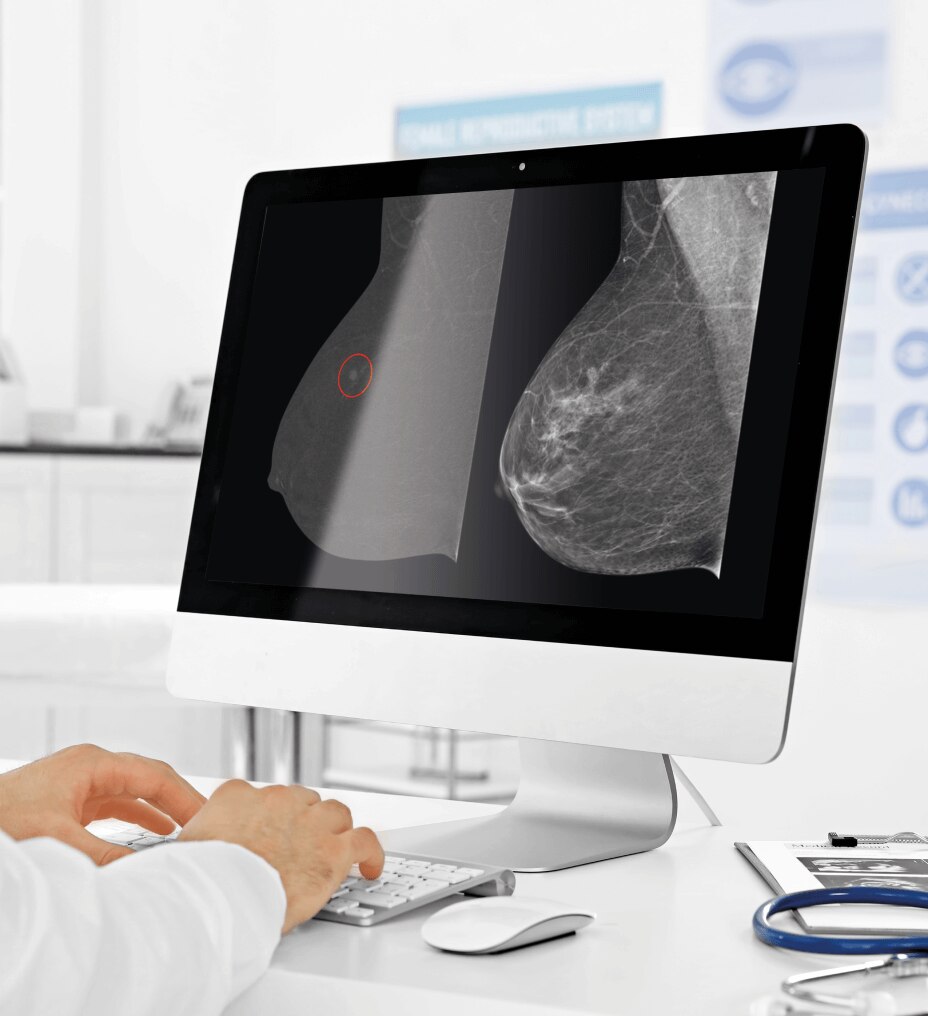

Using ISUOG practice guidelines, SonoLystIR automatically detects recommended views. It identifies anatomy, then selects applicable annotations and measurements. Confirm and data is entered into the Scan Assistant checklist and report, enhancing workflow and reducing variability.